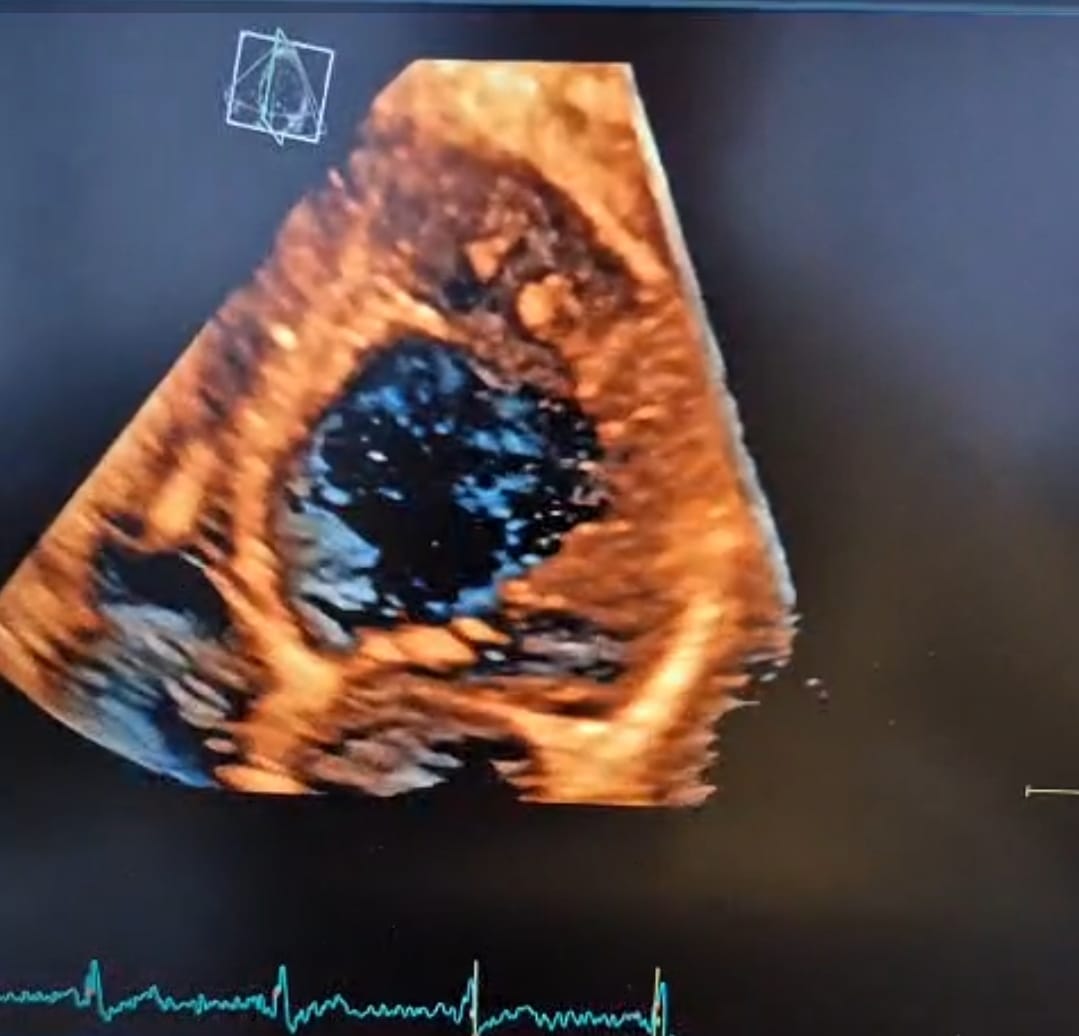

Avaliar o coração de quem utiliza anabolizantes esteróides é diferente do paciente comum, isso deve ser considerado na utilização do método da Ecocardiografia.

Treinar e demonstrar ao médico Ecocardiografista os detalhes da análise do ETT 3D.